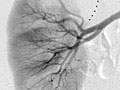

Una angiografía es una prueba radiográfica que utiliza un tinte y una cámara para obtener imágenes del flujo de sangre en una arteria o en una vena. La angiografía puede usarse para observar las arterias o las venas de la cabeza, los brazos, las piernas, el pecho, la espalda o el abdomen. Esta prueba se hace para detectar problemas en las arterias o en las venas.

Durante una angiografía, el médico le introducirá un tubo delgado y flexible en un vaso sanguíneo en la ingle o el brazo. Este tubo se llama catéter. El médico guía el tubo hasta el vaso sanguíneo que se va a examinar. A continuación se inyecta un tinte a través del tubo para hacer que la zona sea más fácil de ver. Se toman radiografías o imágenes de la zona.

Una vez que se haya colocado el catéter, se inyecta el material de contraste a través de él. Es posible que se le pida que inhale y contenga la respiración durante varios segundos. Se tomarán varias imágenes radiográficas, una tras otra. Estas estarán listas de inmediato para que su médico pueda observarlas. Debe permanecer muy quieto para que las imágenes sean nítidas. Es posible que se tomen más imágenes.